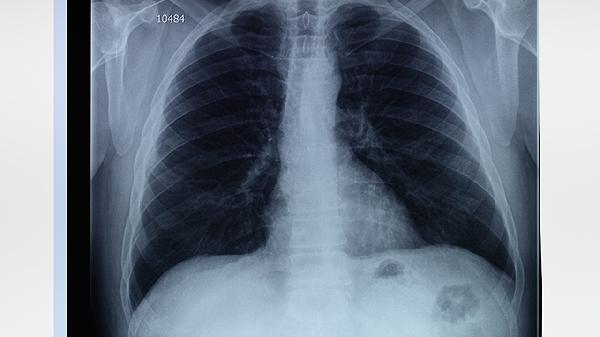

右肺上叶肺大泡是否有事需结合具体病情判断,多数情况下体积较小的肺大泡无明显症状,但体积较大或合并感染时可能引发气胸、呼吸困难等并发症。肺大泡可能与长期吸烟、慢性阻塞性肺疾病、肺部感染等因素有关。

体积较小的肺大泡通常不会引起明显不适,仅在影像学检查时偶然发现。这类肺大泡若无破裂风险或压迫周围组织,一般无须特殊治疗,但需定期复查胸部CT监测变化。患者应避免剧烈运动、高空飞行等可能增加胸腔压力的活动,同时戒烟并预防呼吸道感染。

体积超过一侧胸腔三分之一或位于肺尖部的大泡可能因外力作用破裂导致自发性气胸,表现为突发胸痛、呼吸急促。合并感染时可能出现咳嗽、发热、脓痰等症状。此类情况需通过胸腔闭式引流排出气体,严重者需行肺大泡切除术或胸腔镜手术。反复发作的气胸患者可考虑胸膜固定术降低复发概率。

建议肺大泡患者每6-12个月复查胸部CT,日常避免提重物、屏气等动作。若出现胸痛、呼吸困难等症状应立即就医。合并慢阻肺等基础疾病者需规范使用布地奈德福莫特罗粉吸入剂、噻托溴铵粉雾剂等药物控制原发病。